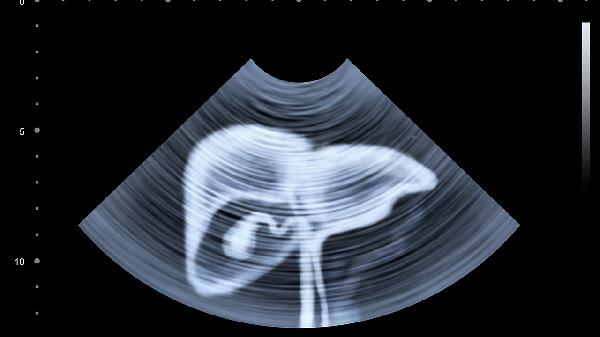

1、右肩持续性疼痛

肝脏本身没有痛觉神经,但肿瘤增大压迫膈肌时,会刺激神经引发右肩放射痛。这种疼痛特点是没有明确压痛点,活动不受限但休息不缓解。